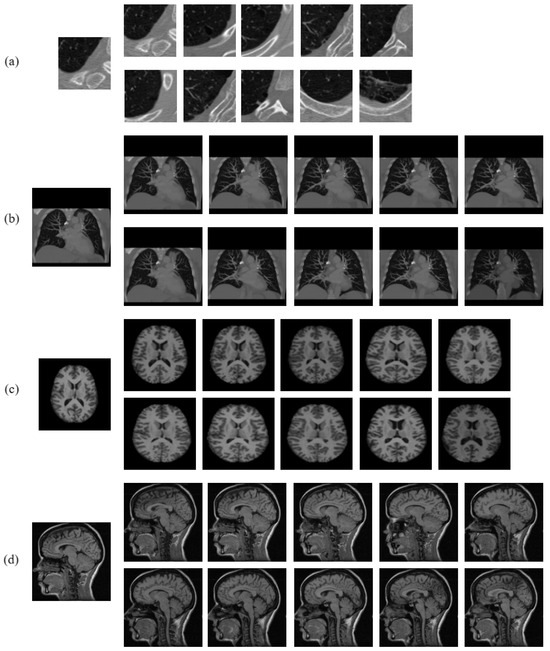

- Firstly, the medical image is transformed to the neutrosophic domain, such that for every input medical image, we obtain three neutrosophic images, i.e., truth (T), indeterminacy (I), and falsity (F).

- Secondly, from each of the T, I, and F images, rotation-invariant and noise-robust texture feature pattern descriptors, , , and are extracted. The computation of the proposed pattern is based on construction of a symmetric neighborhood of members around every pixel at a distance r from it. The parameter r also determines the spatial scale of the , , and patterns, which produces a constant dimensionality histogram at any spatial scale r with sampling points for each neutrosophic image. In our work, texture features are extracted at multiples scales to capture the multi-resolution view of the image.

- Lastly, the final pattern is formed by scale-wise appending of the individual patterns , , and extracted from the T, I, and F images, respectively. In other words, the pattern is formed by appending the patterns , , , and so on, where each pattern is obtained by concatenating the patterns , , and .